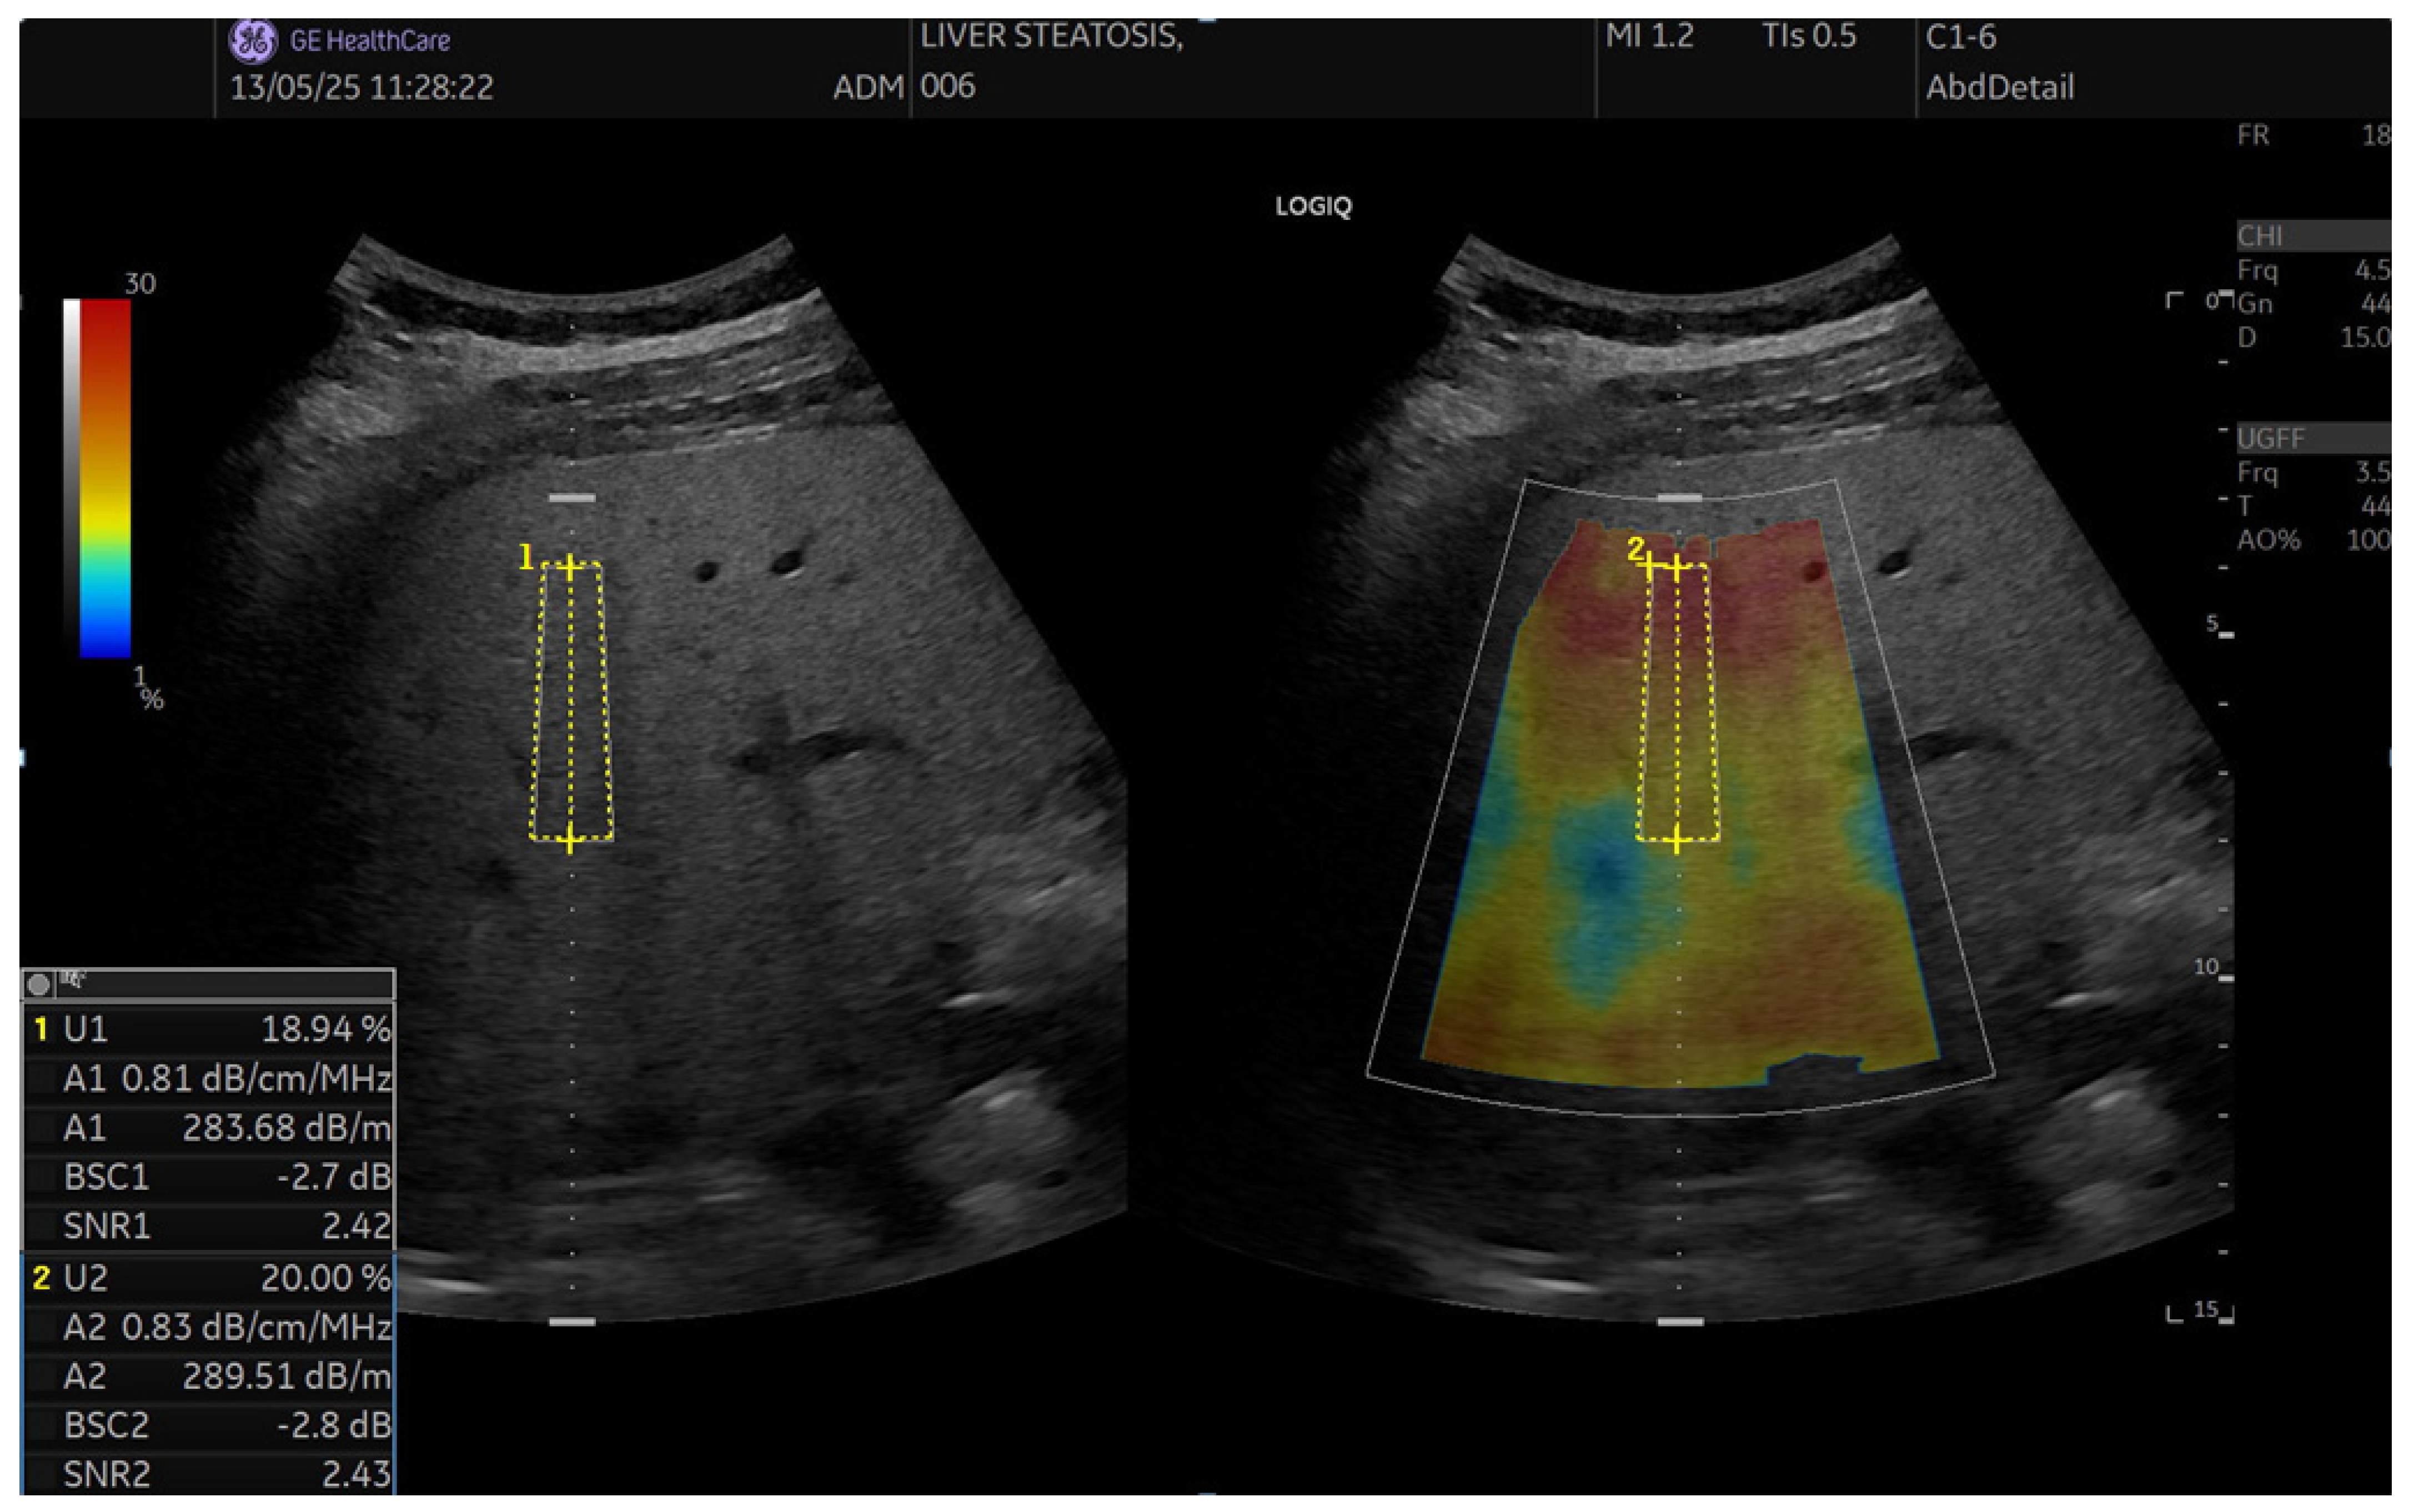

2.5. QUS Protocol (UGFF, AC, BSC, SNR)

2.5.1. Workflow

2.5.2. Ultrasound-Guided Fat Fraction (UGFF)

2.5.3. Attenuation Coefficient (AC, UGAP)

2.5.4. Backscatter Coefficient (BSC)

2.5.5. Signal-to-Noise Ratio (SNR)